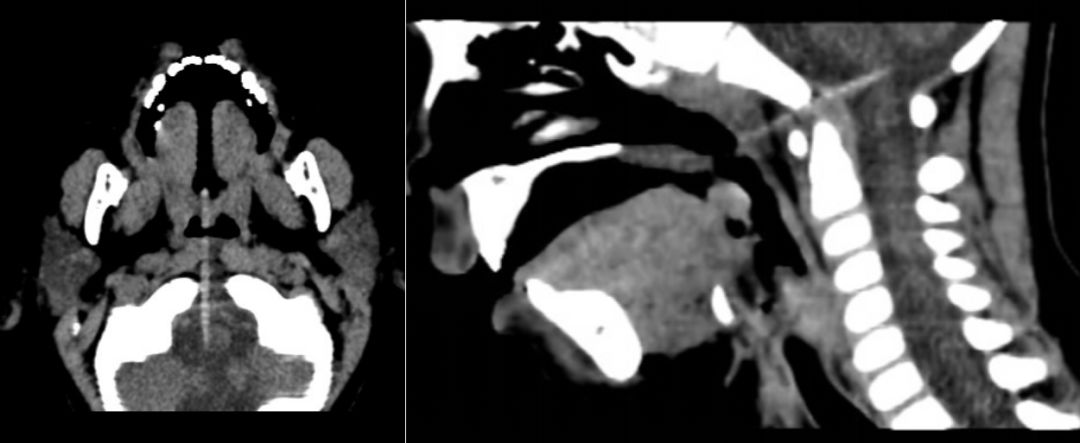

辅检:急诊头颅+颌面部CT示:头颅CT平扫未见明显异常;口腔异物,穿至延髓内,延髓损伤可能(图1)。急诊头颅MRI示:口腔内异物穿至颅内,紧贴延髓右侧,未见伤及颅内大血管,延髓异常信号尚不明显(图2)。急诊血常规:WBC:13.15×10^9/L,N:47.7%,HB:119 g/L,PLT:211×10^9/L,CRP<0.5mg/L。

图1. 头颅CT:水平位可见一稍高密度影的竹签从患儿口腔穿入颅底,并固定于患儿右侧脑干旁;矢状位更清楚地看出竹签从口腔内通过颅底枕骨大孔与寰枢椎之间的间隙插入脑干中。颅内未见明显血肿。